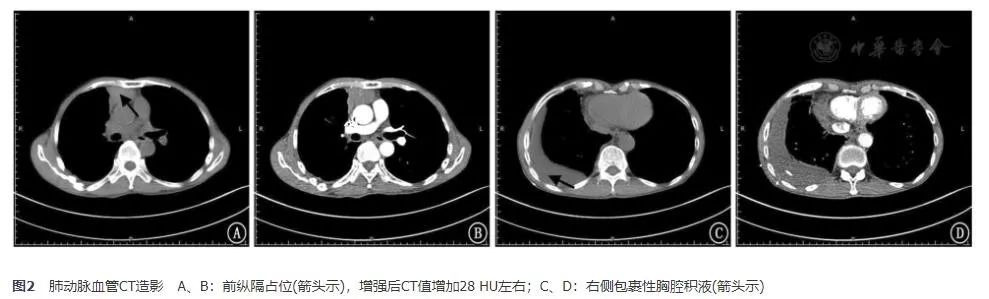

进一步行PET/CT检查,提示:(1)前上纵隔软组织块影伴代谢异常增高,考虑胸腺恶性肿瘤可能,邻近主动脉受累待排;膈区、心膈角、纵隔及右肺门淋巴结转移;右侧胸膜多发转移;右肺内多发小结节影,代谢不高,转移待排。(2)右侧胸腔包裹性积液引流中;右下肺少许炎症。(3)肝多发囊肿;左肾多发高或低密度囊肿。(4)双肾上腺代谢稍高,考虑增生性改变,建议随访。(5)前列腺增生,*丸睾**鞘膜积液。(6)多发椎体异常及含气腔,考虑良性可能大,建议必要时行核磁共振检查(图4)。

图4 PET/CT结果 A:前纵隔、纵隔淋巴结异常代谢增高;B:胸膜、心包异常代谢增高;C:心膈角异常代谢增高;D:右侧胸膜异常代谢增高,右肺结节